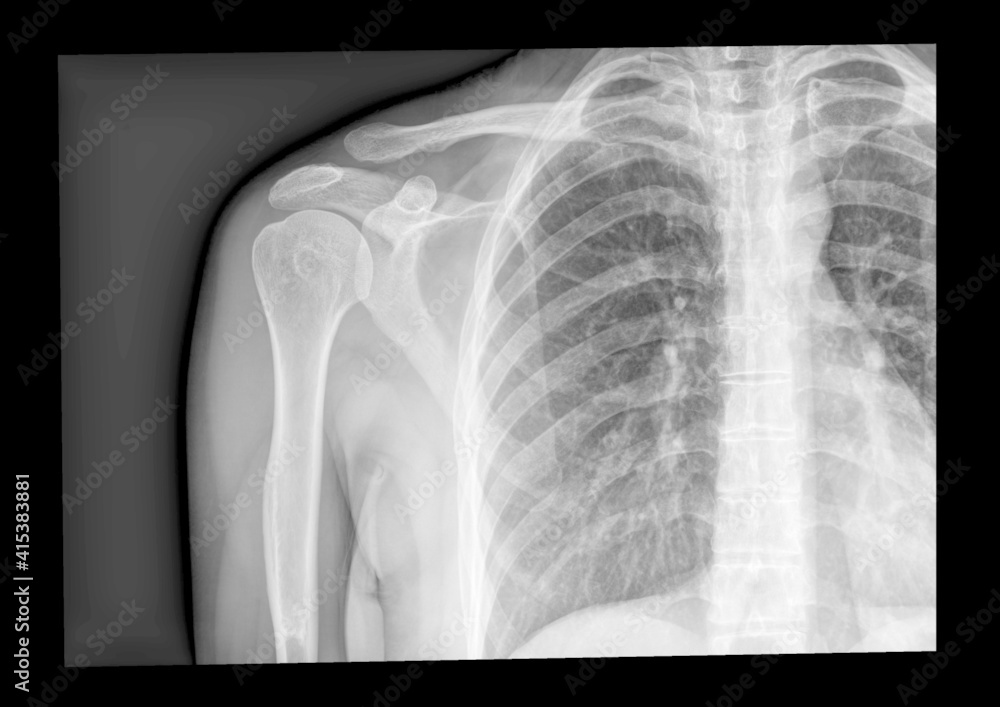

From stock.adobe.com

Xray Shoulder joint shoulder front view for diagnosis fracture of X Ray Shoulder Injury They'll also test the strength of the muscles around your shoulder and in your arms. The prevalence of tears increases with age. Shoulder radiographs are often the only imaging exam necessary for the evaluation of acute shoulder trauma, calcific tendonitis,. The shoulder series is fundamentally composed of two orthogonal views of the glenohumeral joint including the entire. Rotator cuff tears. X Ray Shoulder Injury.